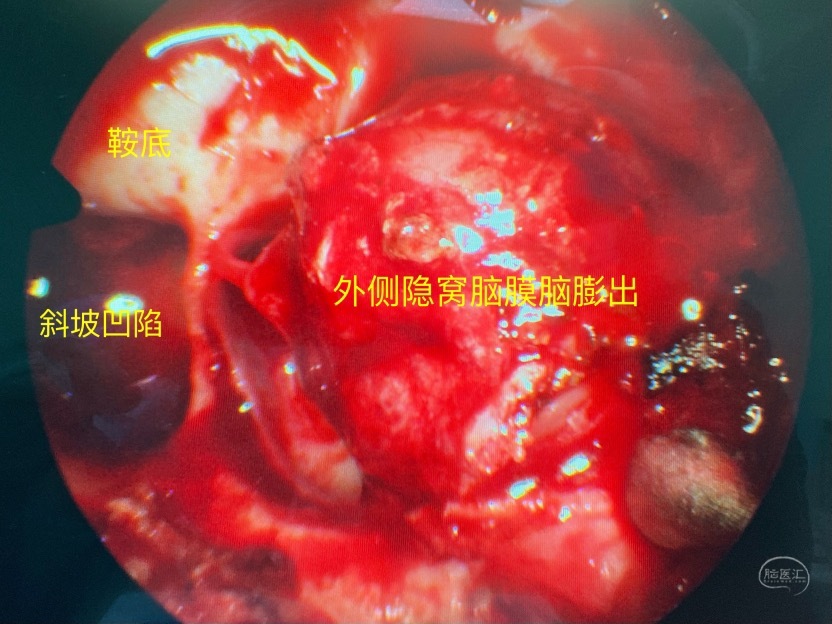

术中证实为蝶窦外侧隐窝的脑膜脑膨出

切除部分膨出脑组织,外侧隐窝因翼突根部的遮挡操作受限

漏口位于颅底侧方区,显露是关键